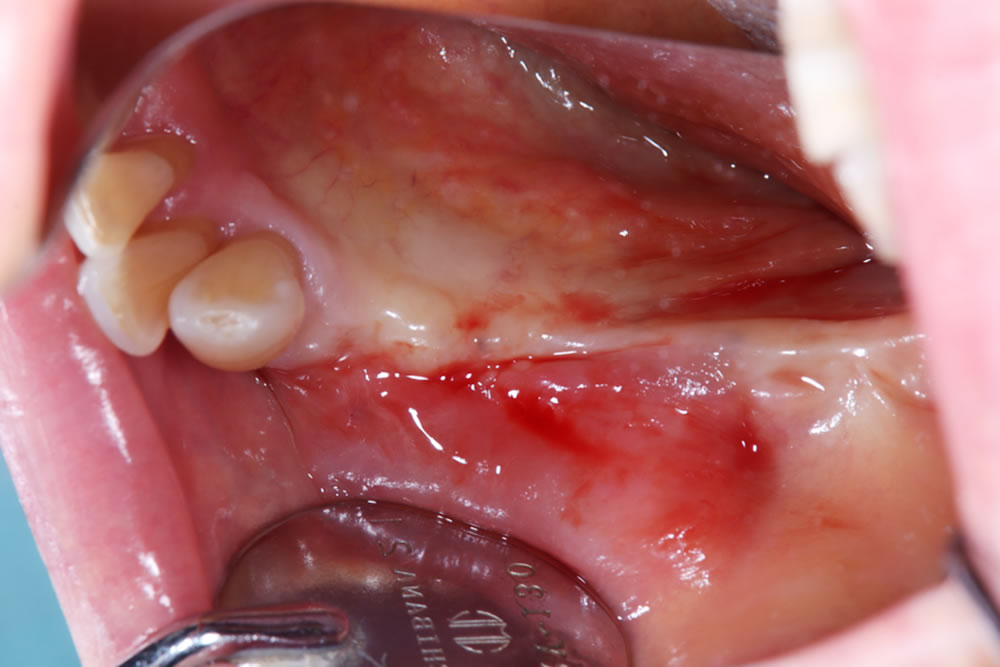

FGG(遊離歯肉移植術)の経過

移植した歯肉は良好に生着しており、上顎口蓋の採取部位についても順調に治癒が進んでいます。

術前は歯肉が非常に薄く大半が可動粘膜でしたが、術後はインプラント周囲に角化粘膜が獲得できました。